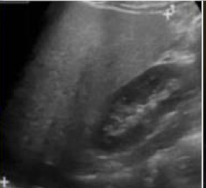

What is this and what type of scan

Ovarian Cyst, Pelvic US